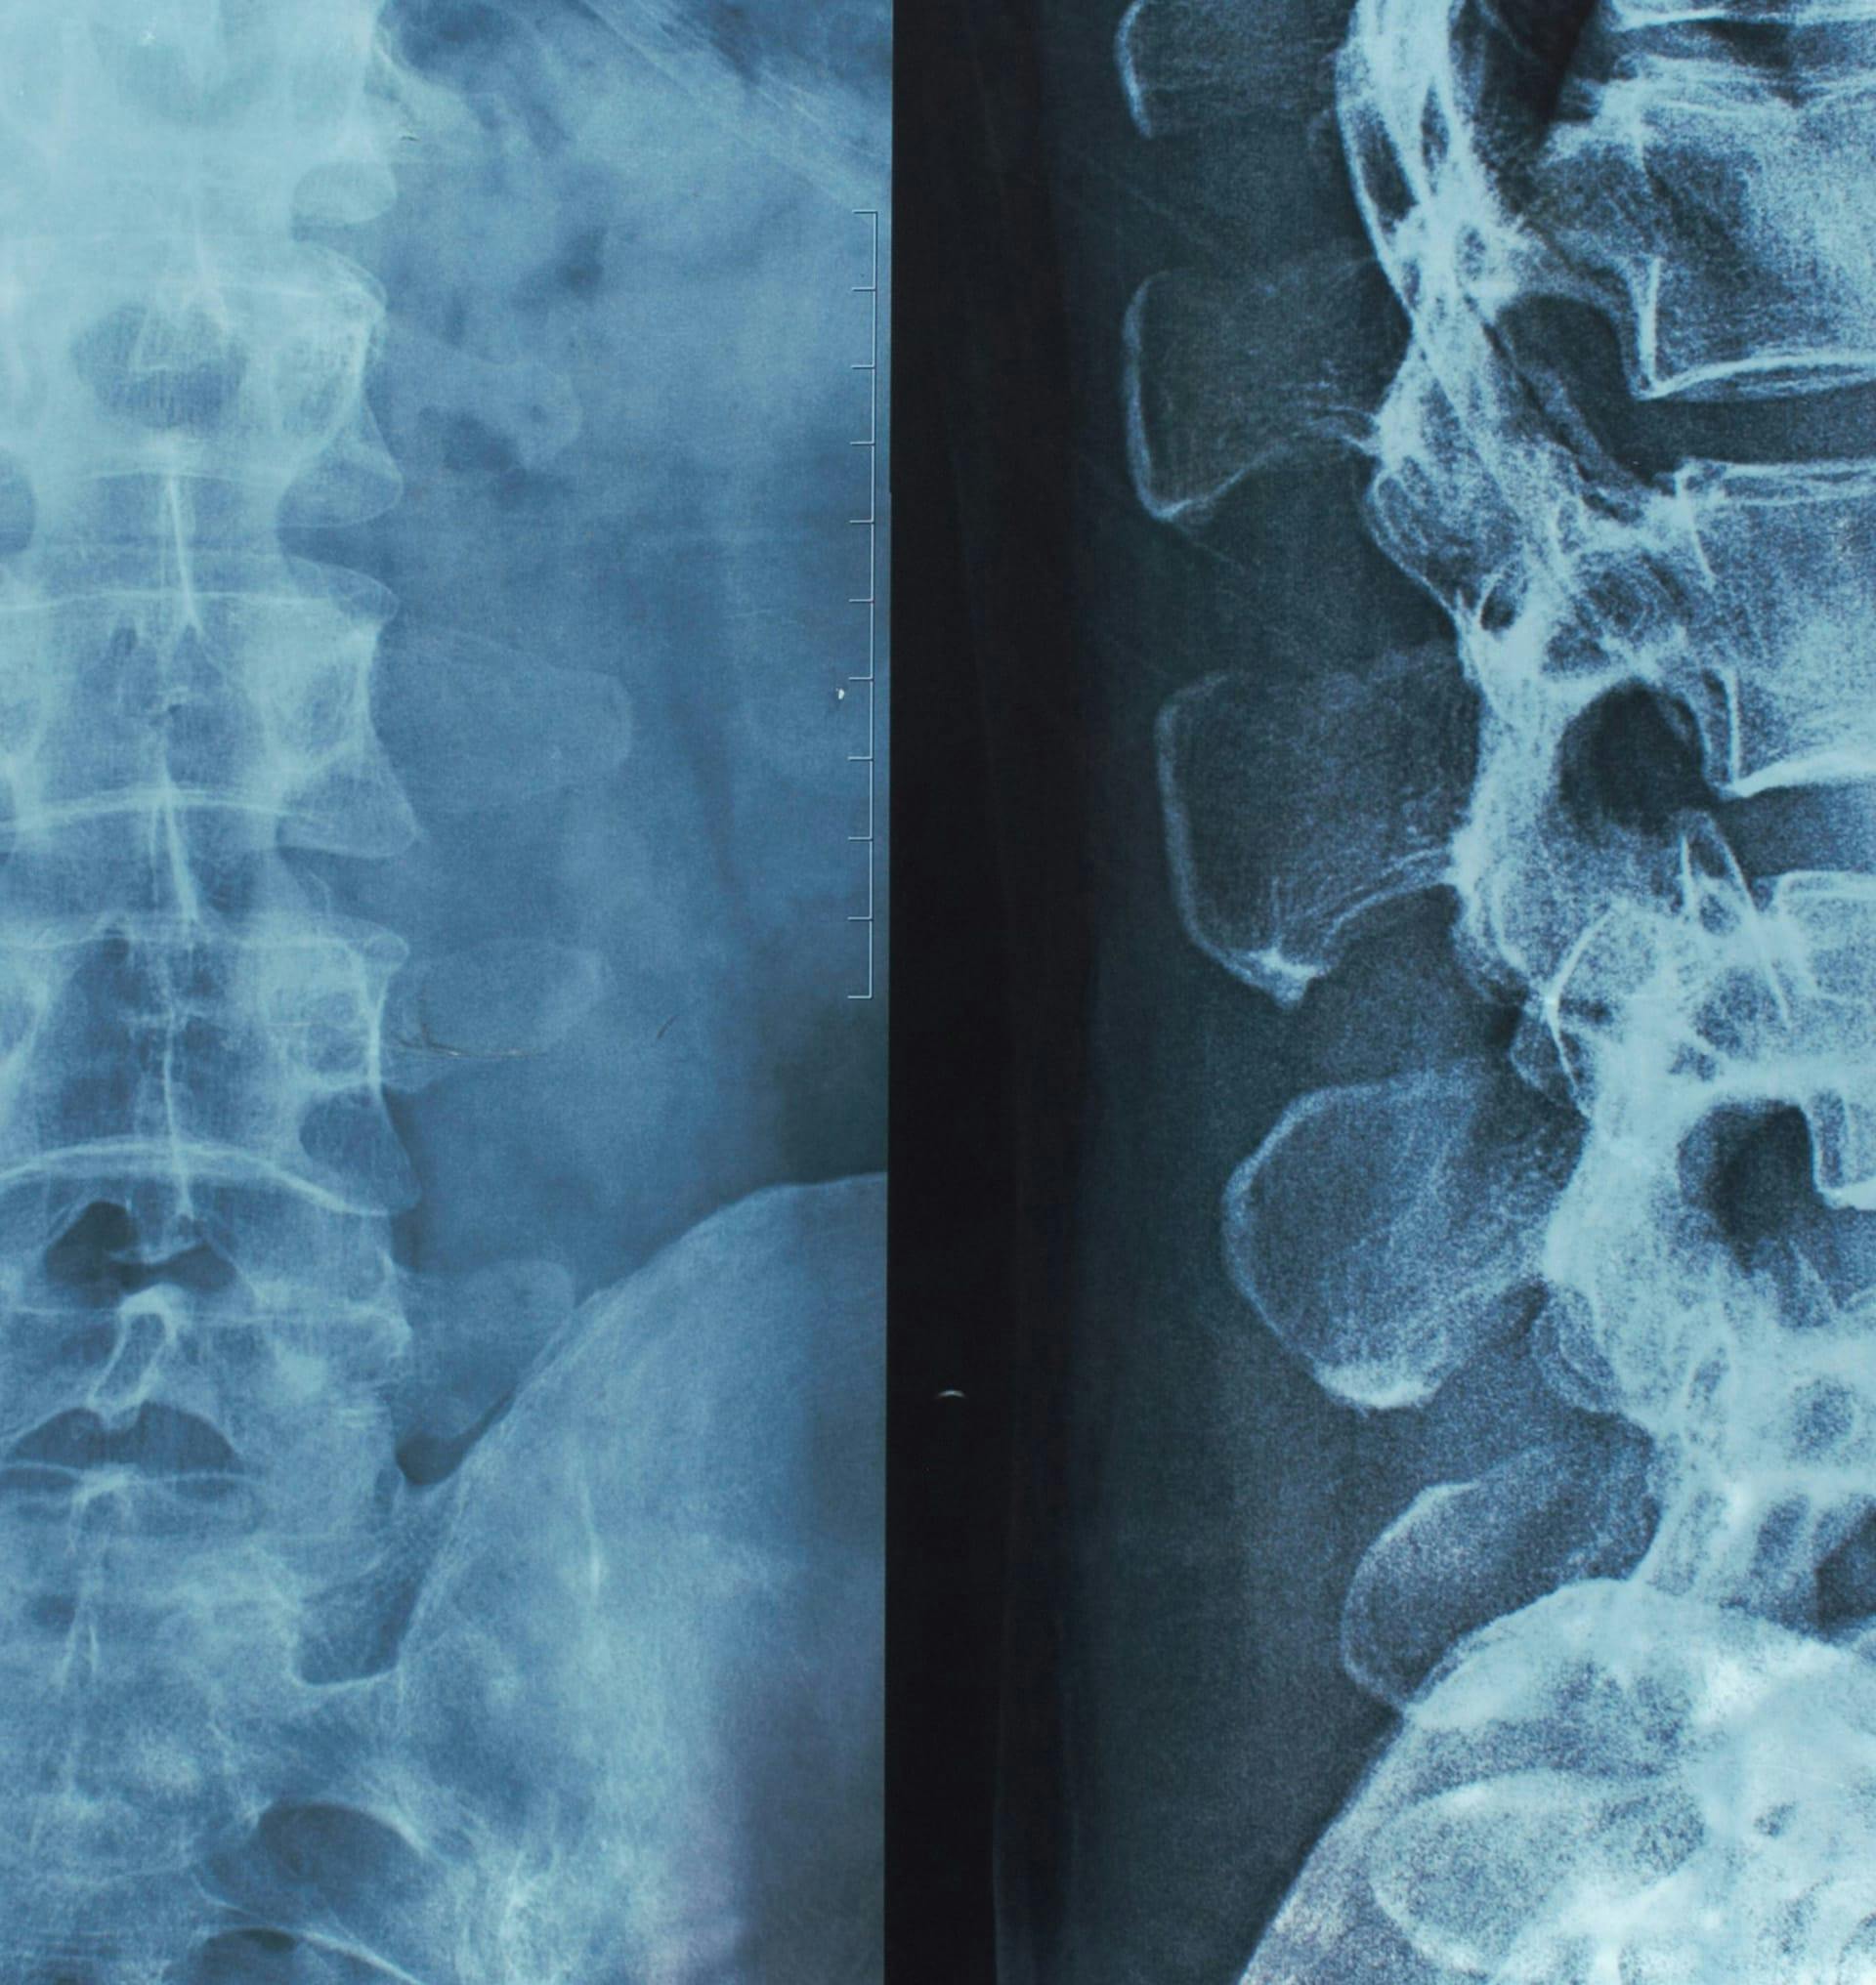

Few injuries can be as devastating to the human body as spinal cord and brain injuries. Paralysis often results from these injuries and, unfortunately, in many cases, will lead to permanent, life-altering disabilities. For people with paralysis, ongoing medical care and a drastic change in the quality of life have become new realities. If there are parties at fault for these accidents, they need to answer for acting negligently and causing paralysis in an innocent victim.

There are many kinds of paralysis, many of which are associated with serious medical conditions. When it comes to spinal cord and brain injuries, however, a few different types are prevalent.